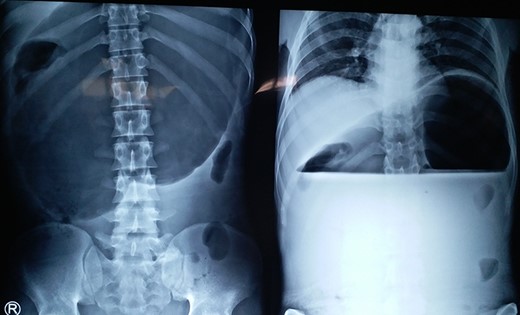

Chest X-ray and CT showing an elevated left hemi-diaphragm with a large sub-diaphragmatic air-fluid level.

A 19-year-old male with no known co-morbidities presented to the emergency department with 2-day history of severe upper abdominal pain and vomiting. He complained of similar episodes over the past 2 years, which used to get relieved spontaneously. On examination, the patient was tachycardic (110 bpm) with normal blood pressure and normothermic. The upper abdomen was asymmetrically distended, non-tender with a tympanic note. The laboratory investigations were within normal limits. Chest X-ray revealed markedly elevated (>4 cm) left hemi-diaphragm, huge gastric shadow with an air-fluid level and shift of mediastinum toward the right side (Fig. 1). Acute gastric volvulus was suspected based on the above finding, which was confirmed with contrast CT. Patient underwent initial laparoscopic evaluation, which was converted to open procedure. Intraoperatively, there was an organo-axial volvulus without any vascular compromise secondary to diaphragmatic eventration. It was de-rotated, decompressed and anterior abdominal wall suture gastropexy done. The freely mobile stomach was further reinforced with sham (trans-seromuscular) gastrojejunostomy. Left diaphragmatic eventration was plicated with polypropylene suture number 1 (Fig. 2) for which it required open conversion. Postoperative period was uneventful and discharged on Day 6. At 16-month follow-up, patient is doing absolutely fine.